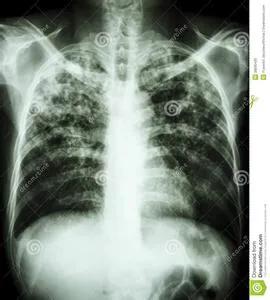

影像学检查包括X线胸片和胸部CT。前面讲的几种主要类型的肺结核,各自有不同的表现:

- 原发型肺结核的典型表现是肺原发病灶、淋巴管炎和肿大的肺门和纵膈淋巴结组成的“哑铃状”阴影。

- 急性血行播散型肺结核在X线胸片上表现为散布于两肺野的,分布、密度、大小“三均匀”的粟粒状阴影,故又叫粟粒型肺结核。

- 继发性肺结核是最常见的,其X线表现也是最复杂、多变的,有时很难跟普通的肺炎相鉴别。

CT相对于胸部X线片来说,会更清楚,分辨率更高,能看到更小的病灶,但存在着辐射比胸片更大的缺点。

肺部影像学检查,大多数情况下能提供基本准确的肺结核的诊断,但是仍然有少部分人需要完善进一步的检查,才能使结论更可靠。